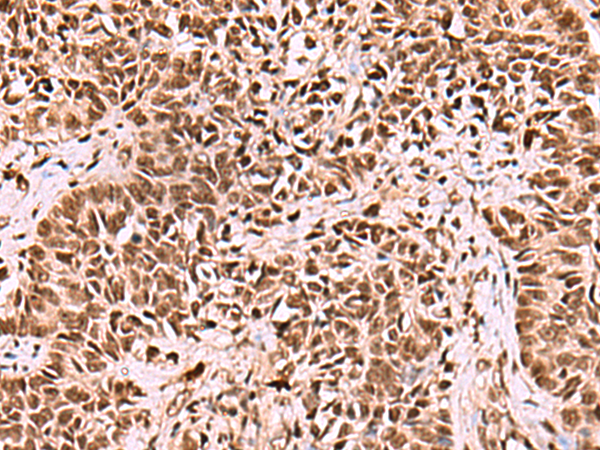

IHC positive control:

Human ovarian cancer and Human thyroid cancer

IHC Recommend dilution:

70-350